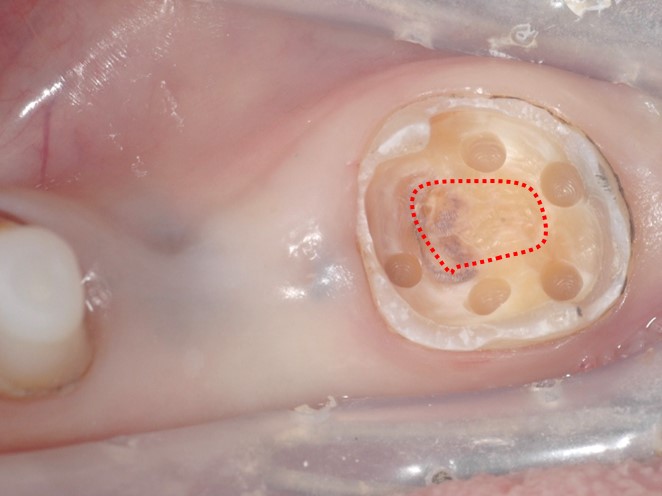

まず周りにホール(穴)を形成します。(下写真:赤点線部分に歯髄がある)